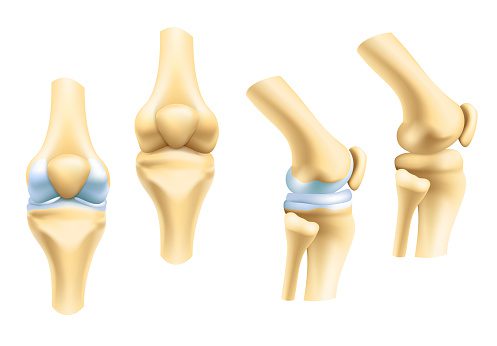

Cartilage is a flexible, elastic tissue that coats the surfaces of the bones in the joints to keep them working smoothly and protected. It is also found in the rib cage, ears, nose, bronchial tubes and other areas. It is also between the bones of the spinal column and a slipped or bulging ‘disc’ is when the cartilage becomes misplaced causing a great deal of pain. As nail professionals it is always important to sit correctly when working as long term spine curvature can cause this condition.